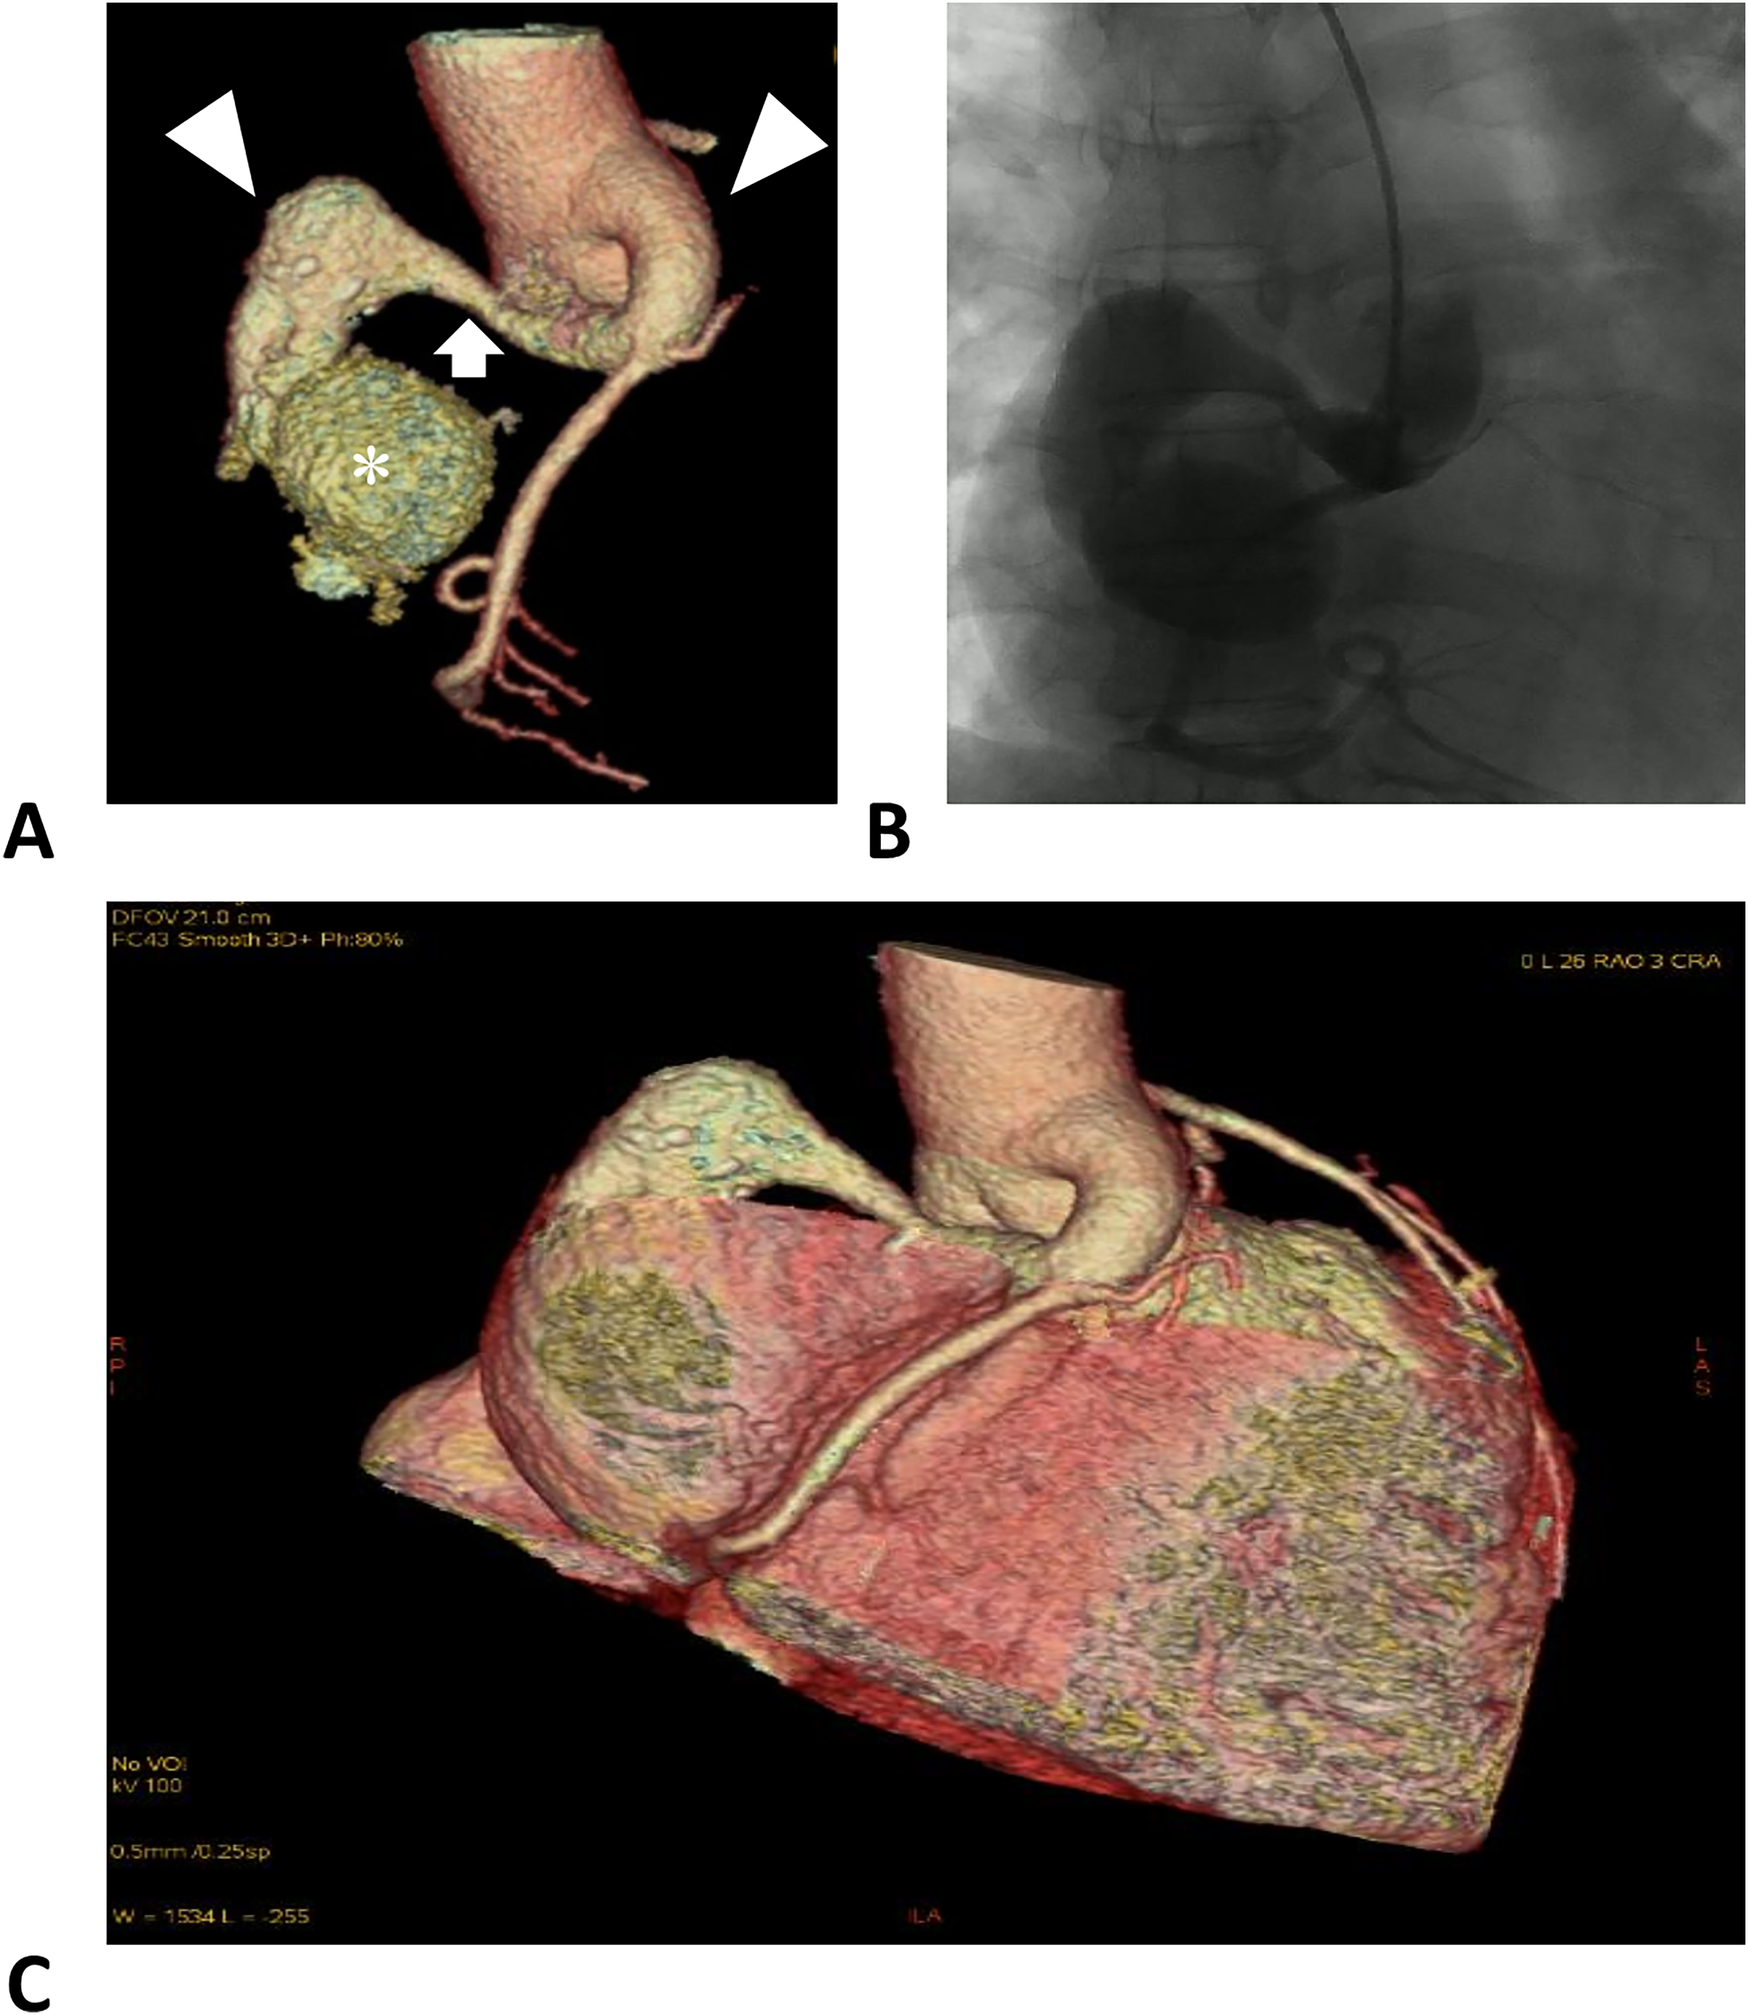

Computed tomography angiography and digital subtraction angiography showed a “dumbbell” RCA ectasia at the origin (ID 14 mm) and the fistula wall in the RA (ID 37mm × 36 mm, forming a fistula sac), and the connecting segment was normal (Figure 1, Supplementary Material Video S1). The ostium from the RCA fistula sac to the RA was 10 mm in width, facing the inferior vena cava. Transesophageal echocardiogram (TEE) showed a continuous flow enhanced during diastole at the entrance (peak velocity 2.5 m/s) and exit (peak velocity 1.8 m/s) of the RCA fistula sac (Figure 2, Supplementary Material Videos S2, S3). Her atria (left ID 44 mm, ref. 27–38 mm; right vertical diameter 62 mm, ref. <53 mm), left ventricle (end of diastole ID 61 mm, ref. 39–52 mm), and pulmonary artery (ID 32 mm, ref. 12–26 mm) were enlarged.

Figure 1

Right coronary artery images. (A) Computed tomographic angiography of the RCA. The left and right triangles denote the distal and proximal aneurysmal segments of the RCA. The arrow denotes a normal segment between the dilations, forming a dumbbell-shaped ectasia. The asterisk denotes the fistula sac formed in the right atrium. (B) Digital subtraction angiography of the RCA. (C) Reconstruction of the coronary arteries and the heart, illustrating the positional relationship.